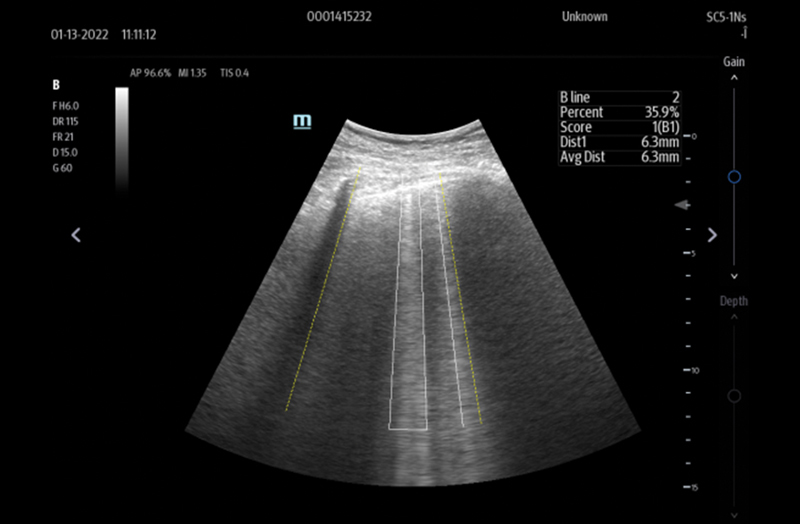

The TE7 Max Ultrasound System is designed to maximize your capabilities in demanding Point of Care environments. With its thoughtful industrial design and best-in-class image quality, the

TE7 Max provides a superior user experience during rapid clinical assessments and procedures taking place at the patient’s bedside

or on the go.

The TE7 Max boasts a large 21.5” vertically oriented high-definition display and a sealed touch-based interface to optimize visualization and accessibility when every second counts. The TE7 Max also incorporates a comprehensive suite of artificial intelligence (AI) powered Smart Tools and workflow enhancement software (iWorks™ Protocol) making efficiency and reproducibility the expectation for all end users.